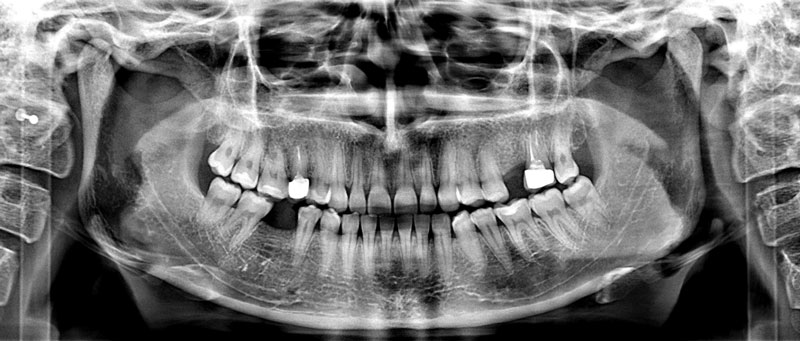

Спектр рентгенодиагностических услуг в нашей клинике широк – от прицельного снимка одного зуба, ортопантомограммы, до объёмного 3Д исследования смежных областей (височно-нижнечелюстные суставы, кости лица и черепа, верхнечелюстные ( Гайморовы ) пазухи.

Обращаем ваше внимание - диагностика стоматологических заболеваний в нашей клинике производится с использованием высокоточного рентгеновского аппарата PLANMECA ProMax 3D Plus, что позволяет получить трехмерное цифровое изображение для тщательного изучения клинической ситуации при низкой лучевой нагрузке пациента.

С помощью рентгена врач может увидеть состояние каждого зуба и его корней, рядом расположенные органы и ткани. Процедура помогает поставить правильный диагноз перед началом лечения и позволяет оценить качество работы стоматолога во время лечения и после его окончания, что очень важно при пломбировании каналов, удалении зубов, установке имплантатов.